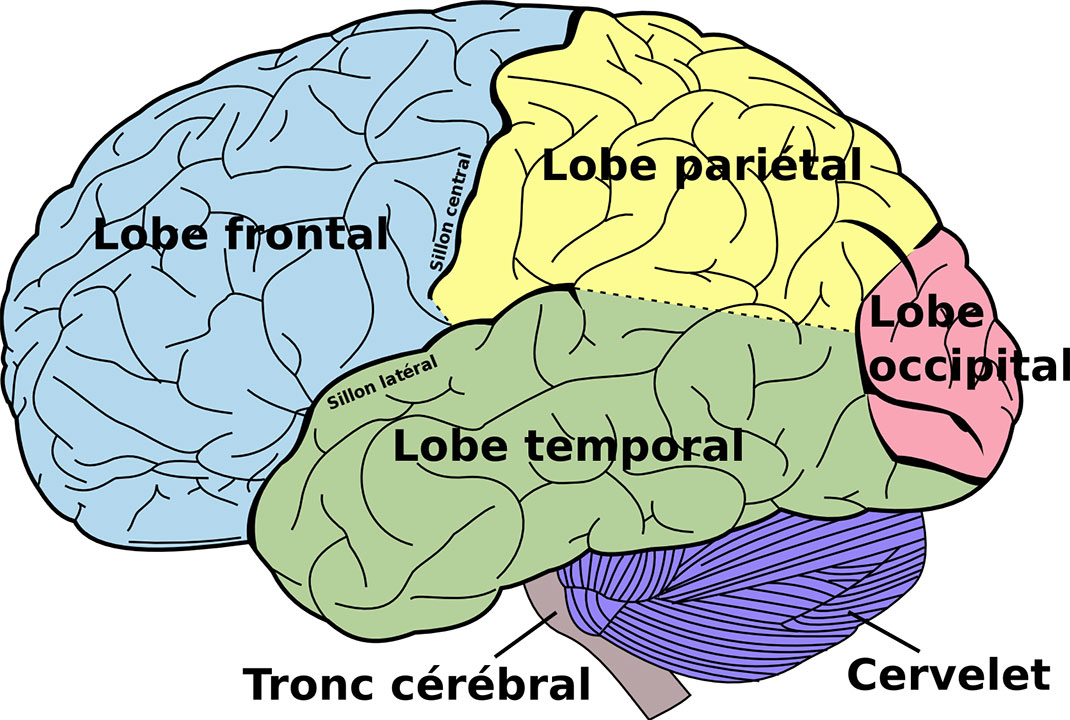

Le cortex insulaire constitue une partie du cortex cérébral et forme l’un des lobes du cerveau. Sa fonction exacte est encore mal connue, mais il est associé au système limbique ainsi qu’à certaines émotions telles que le dégoût et la dépendance ou encore à certains phénomènes tels que la régulation de la pression artérielle.

Lors de la modulation de la pression artérielle sur plusieurs sujets, ce qu’observent Paul Macey et son équipe au moyen d’une IRM du cerveau, est une différence de réaction entre la partie avant droite du cortex insulaire selon que celui-ci est situé dans la boîte crânienne d’un homme ou d’une femme. Chez les hommes, cette zone s’est trouvée être suractivée par l’augmentation de la pression artérielle quand, chez les femmes, celle-ci restait muette.

Aussi, loin de viser à la formulation de jugements de valeur dangereux et sexistes, ces conclusions scientifiques doivent être prises en compte parce qu’elles peuvent servir à une meilleure appréhension des différences sexuelles en matière de maladies cardiovasculaires ou neurologiques et donc, à une meilleure prise en charge médicale. Si ce sujet vous intéresse, vous pouvez découvrir cette carte du cerveau humain qui est d’une précision incroyable.